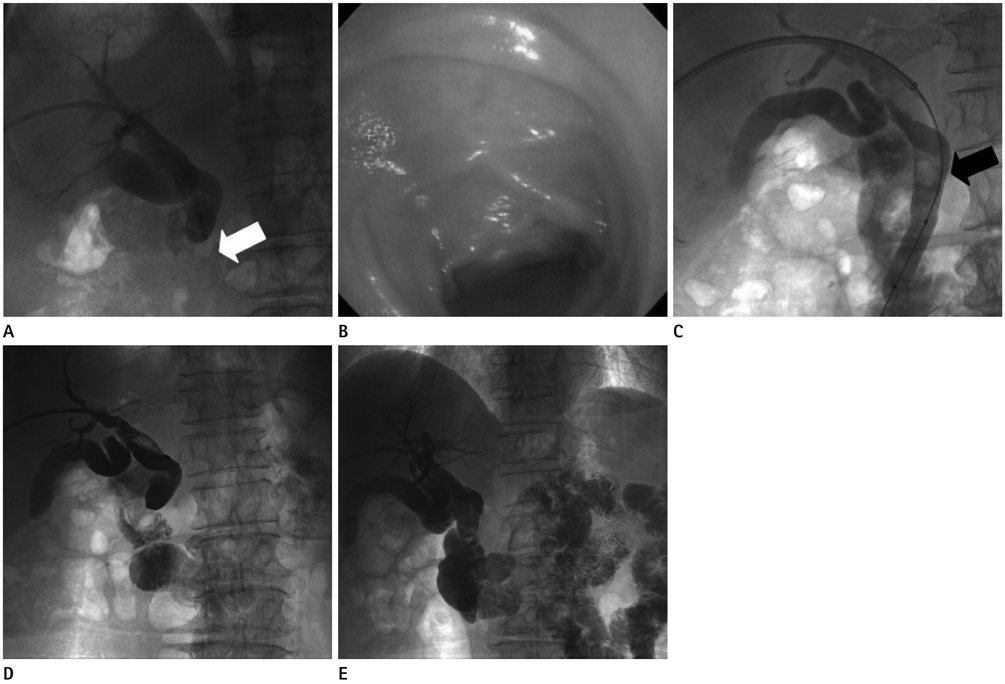

Figure